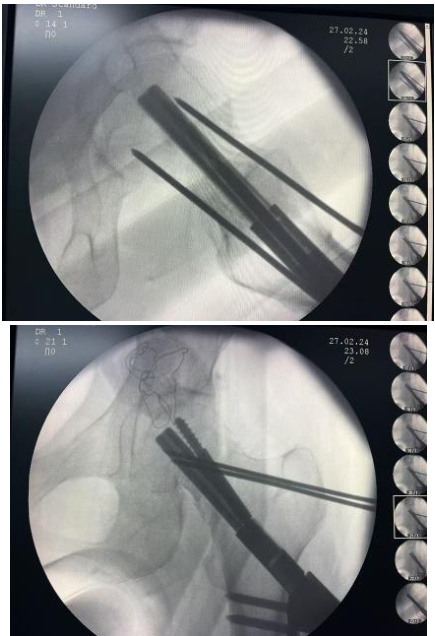

观察组患者为 ERAS+FNS 内固定治疗,手术方式如下:大转子下侧朝患者股骨颈上方将一枚克氏针进行植入,从而对股骨颈骨折进行临时固定,做纵向手术切口,对骨膜进行切开,使股骨外侧壁获得完全显露,再以髓腔钻于导针的辅助下进行扩孔操作,通过连接杆顺利使动力棒置入于手术通道中,对其进行适当敲击,从而抵达股骨头颈髓腔当中,外侧钢板进行妥善放置,确保和股骨外侧皮质保持良好的贴合,利用锁定螺钉进行固定,继续沿导向器扩孔,并将抗旋钉进行置入,透视下观察内固定位置,理想后可将导针以及抗旋克氏针进行取出。对照组患者采用 ERAS+ 空心加压螺钉(CCS)内固定治疗,手术方式如下:术中尽可能通过倒置三角形为患者经皮置入导针,实施正侧位透视,观察位置满意后,可继续于导针镜皮位置做手术切口,沿导针进行扩孔以及弓丝操作,将 3 枚空心加压螺钉进行拧入,最后对骨折端进行加压固定。两组患者的ERAS 处理方法如下:组建ERAS团队,成员包含手术医生、护士以及麻醉师、心理咨询师、康复治疗师等,共同制定围术期管理方案,包含心理护理、疼痛管理、饮食管理、早期康复锻炼等。患者均于术前 6 小时禁食以及 2 小时禁饮,术后 6~12 小时遵循循序渐进原则进行逐步的营养支持。观察组患者术后第 1 日起可进行逐步的康复活动,术后第 3 天可恢复至扶拐行走以及下肢部分负重活动,后续结合恢复情况逐步延长活动时间。待 X 线片复查骨折愈合后可恢复完全负重。对照组术后 1~6 天可从床上患肢活动起,逐步扩大范围,延长时间,还可通过双上肢牵引床的辅助完成吊环练习,抬高臀部练习。拆线后可逐步增加活动强度,扩大活动范围。如若骨折较为稳定可于术后第 4 周起进行扶拐下床活动,患者 X 线片复查骨折愈合后方可恢复完全负重。